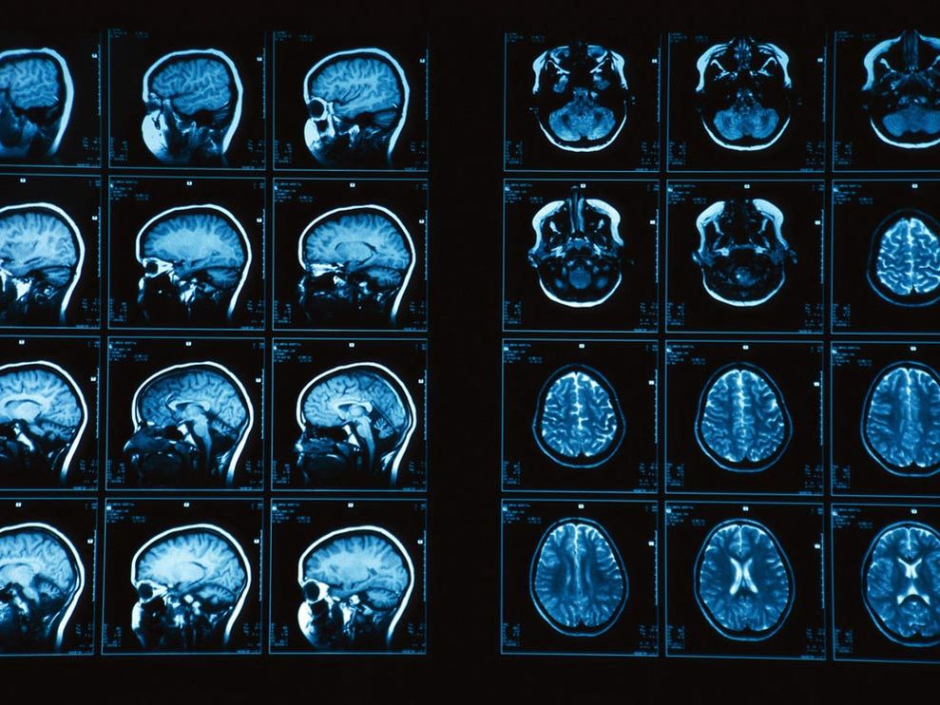

As much as 67 MRI scans were fed to the program based on which the computer takes the disease. The computer drew patterns from the 67 MRI scans (38 from Alzheimer’s patients and 29 healthy samples). After coming up with the program, the team went on to test it. Brain scans from about 148 individuals were taken and provided as an input to the program. Of the total 148 samples, 48 were from individuals suffering from pre-Dementia stages while the rest of the samples were healthy. The program was able to correctly detect Alzheimer’s 86% of the total time.